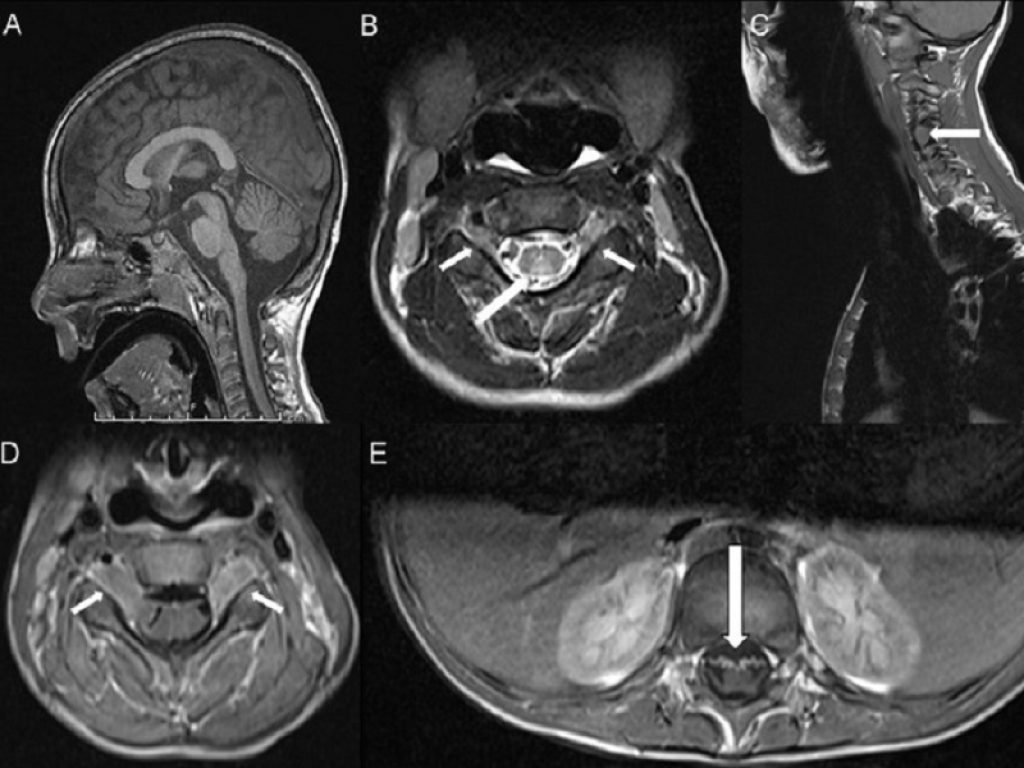

“La scoperta di SLC52A2 e SLC52A3, i geni coinvolti nella patogenesi della malattia, è stata fondamentale per comprendere i meccanismi che sottendono la carenza della riboflavina [più conosciuta come vitamina B2, N.d.R.], fondamentale per vari processi metabolici”, spiega il prof. Enrico Silvio Bertini, dell’Unità di Malattie Neuromuscolari e Neurodegenerative dell’Ospedale Bambino Gesù. “Gli individui colpiti da RTD hanno difficoltà ad assorbire la vitamina B2 da parte di tutti i tessuti, e specialmente a livello delle cellule nervose e perciò sviluppano una sintomatologia motoria importante che conduce a paralisi progressiva di alcune aree del cervello [in particolare la zona ponto-bulbare, N.d.R.], insufficienza respiratoria, debolezza muscolare con coinvolgimento dei nervi cranici motori e sordità”.